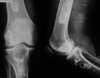

40

22 year old patient. Give 3 differentials in order of likelihood.

1. Infarct 2. Enchondroma 3. Chondrosarcoma

41

43 year old patient. Give 3 differentials in order of likelihood.

1. Chondrosarcoma (>40yrs) 2. Infarct (serpiginous contour) 3. Enchondroma